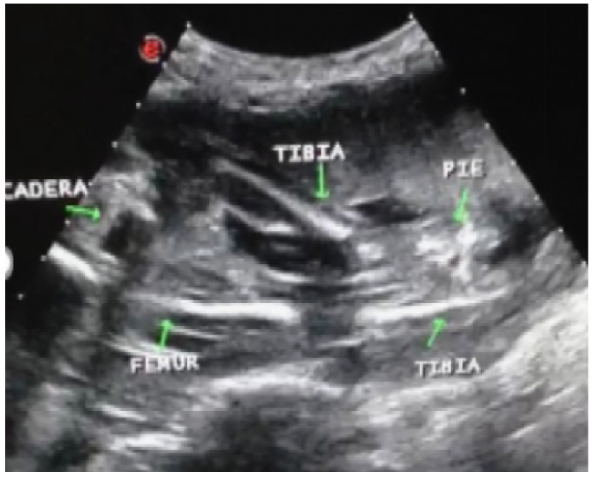

Se trata de paciente de 19 años, sin antecedentes familiares y personales conocidos, pareja con antecedente de paladar hendido. Fecha de ultima menstruación incierta, embarazo no controlado, acude a especialista en Obstetricia y Ginecología quien en vista de hallazgos ultrasonográficos de presencia de quistes de plexos coroides en neurocráneo fetal es referida a la unidad de Perinatología Medicina Materno fetal del Hospital Materno-Infantil “Dr. José María Vargas” donde se realiza evaluacion ultrasonográfica con equipo marca ESAOTE MYLAB 70 XVISION transductor convex 3,5 mHz evidenciando feto único en situación longitudinal, presentación podálica, dorso a la derecha, biometría fetal compatible con gestación de 22 semanas. En polo cefálico al evaluar neurocráneo en el plano axial transventricular se aprecia en el atrio ventricular cerebral a nivel de los plexos coroides imágenes anecoicas, redondeadas, bilaterales, sugestivas de quistes de los plexos coroides, el cual es considerado un marcador de cromosomopatías. Columna vertebral indemne. Cuello sin alteración. Tórax normo configurado. Extremidades superiores presentes y completas manos de difícil evaluacion por posicion fetal. Abdomen normal, estómago lleno, vejiga llena. Sexo masculino. Extremidades inferiores asimétricas, con acortamiento de la izquierda a expensas de ausencia de fémur, tibia y peroné normales cercanos a pelvis ósea (figura 1). Extremidad inferior derecha completa. Con peso estimado fetal de 586 gr. Placenta anterior, de 22 mm de grosor, grado I. Cordón umbilical 3 elementos. Líquido amniótico normal. Doppler de arterias uterinas adecuado a edad gestacional.

Se concluye estudio Ultrasonográfico Perinatal con impresión diagnostica de: Gestación intrauterina simple de 22 semanas, Quistes de plexos coroides, Defecto proximal intercalado tipo 2: Aplasia de Femur izquierdo.